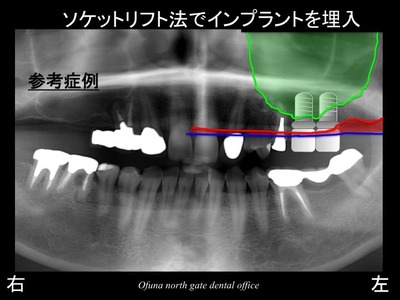

以下がソケットリフト法 でインプラントを埋入した直後です。

ソケットリフト法 の状態を拡大して見てみましょう!

以下の丸で囲んだ部位を拡大します。

拡大したところです。

この写真に骨の状態と上顎洞の線を書いたのが以下です。

ソケットリフト法 により以下の青線まで上顎洞が押し上げられました。